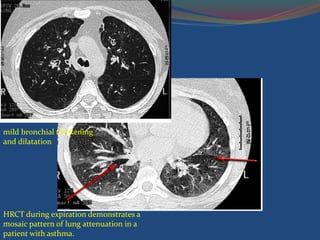

Role of HRCT

 Characteristic CT findings

 Bronchial dilatation



 Bronchial wall thickening

 Mucoid impaction

 Cylindric bronchiectasis

 Centrilobular bronchiolar abnormalities such as tree-in-bud

 Patchy areas of mosaic perfusion

 Regional areas of air-trapping on expiratory scans

mild bronchial thickening

and dilatation

HRCT during expiration demonstrates a

mosaic pattern of lung attenuation in a

patient with asthma.